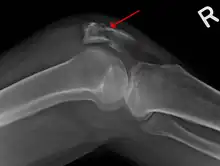

A fracture of the patella seen on a lateral view

A vertical patella fracture with the fracture line marked by a black arrow

Diagnosis is based on symptoms and confirmed with X-rays.[3] In children an MRI may be required.[3]